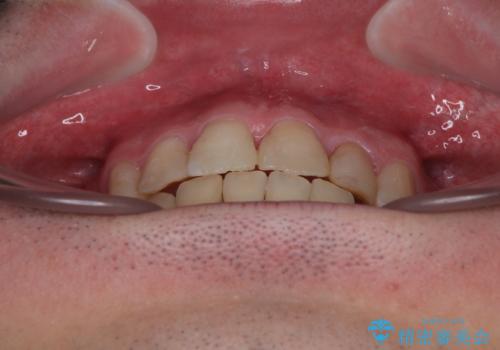

2年半の治療期間を想定しており、予定通りの期間で無事に終了することができました。

唇や顎先に力を入れないなくてもスムーズに唇を閉じることができるようになりました。